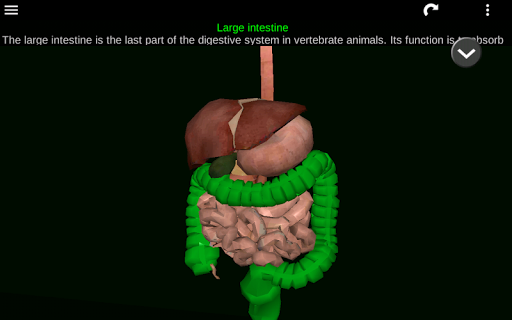

* Digestive system, including the stomach, small intestine, large intestine, and an animation of this system.

* Descriptions of each organ.